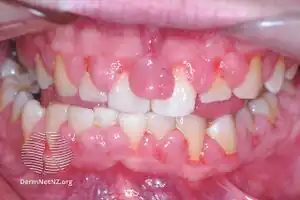

Gingivitis, a common cause of inflammatory gingival enlargement. | |